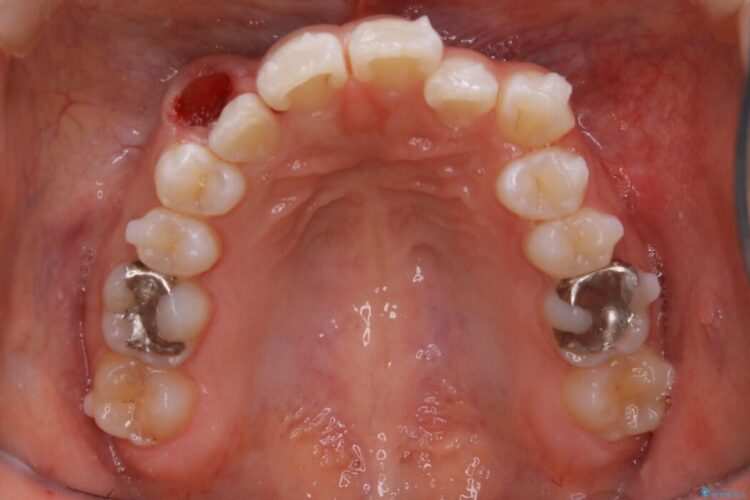

診査したところ叢生だけでなく生まれつき永久歯の欠損、いわゆる先天欠如により歯の本数が少ないため噛み合わせなどにも影響が出ている状態でした。

特殊な状況からの矯正治療となるため、抜歯する本数や位置、歯列を整えるにあたって必要なスペースの確保を慎重に計画し、インビザライン コンプリヘンシブパッケージでのマウスピース矯正を行いました。

笑った時の歯の見た目がきれいになりとても喜んでいただけました。